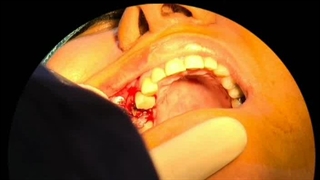

دکتر ابراهیم محمدی جراح و متخصص فک و صورت در تهران هستند. در این ویدئو می‌توانید مراحل و نمونه کار ایمپلنت دندان توسط ایشان را مشاهده کنید.

برای رزرو نوبت مشاوره و ایمپلنت دندان با دکتر ابراهیم محمدی در تهران می‌توانید رو لینک زیر کلیک کنید: